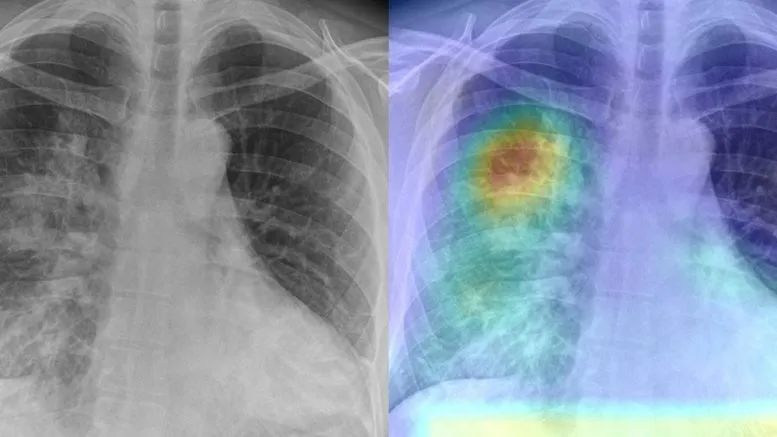

我们不能因为封锁隔离而放弃基本的科学原则,人工智能既不是呼吸机,也不是疫苗,更不是药丸。值得注意的是,根据一些大多数由没有临床经验或不具备医学能力的工程师和计算机科学家创建的医学影像小数据集,有些网站甚至提供了关于如何从 X 射线扫描中高精度地检测出 COVID-19 的建议,甚至还有一些未经同行评议的论文,用 “COVID-Net” 这样的夸张名字为他们的解决方案进行 “洗礼”。这类论文往往未经证实,也未经放射科医生的实验指导,甚至在数据集的创建者还没来得及对其收集数据的过程进行足够解释的情况下,这些研究就匆匆公之于众了。

近年来,人工智能在处理医学影像方面取得了实质性的进展,但新冠疫情大爆发期间,似乎出现了这样一种危险的趋势:一些人仓促地使用存在瑕疵的、有问题的数据来训练针对 COVID-19 的人工智能解决方案,这一做法不仅对患者和医生没有任何帮助,而且还会损害人工智能的声誉。

由于这类数据的可获得性,以及基础人工智能知识和工具存在的普遍性,许多人工智能爱好者和初创公司已经冲动地开始研发从 X 光照片中检测 COVID-19 的解决方案。

有些网站和博客甚至提供了关于如何从 X 射线扫描中高精度地检测出 COVID-19 的建议,还有一些人给出了从 X 光照片中检测 COVID-19 的教程。

甚至还有一些未经同行评议的论文,更进一步,用 “COVID-Net” 这样的夸张名字为他们的解决方案进行 “洗礼”。这种类型的工作通常缺乏许多实验细节,来解释如何通过极少数患者的医学影像图像满足深度神经网络的需求。

这类论文往往未经证实,也未经放射科医生的实验指导,甚至在数据集的创建者还没来得及对其收集数据的过程进行足够解释的情况下,这些研究就匆匆公之于众了。